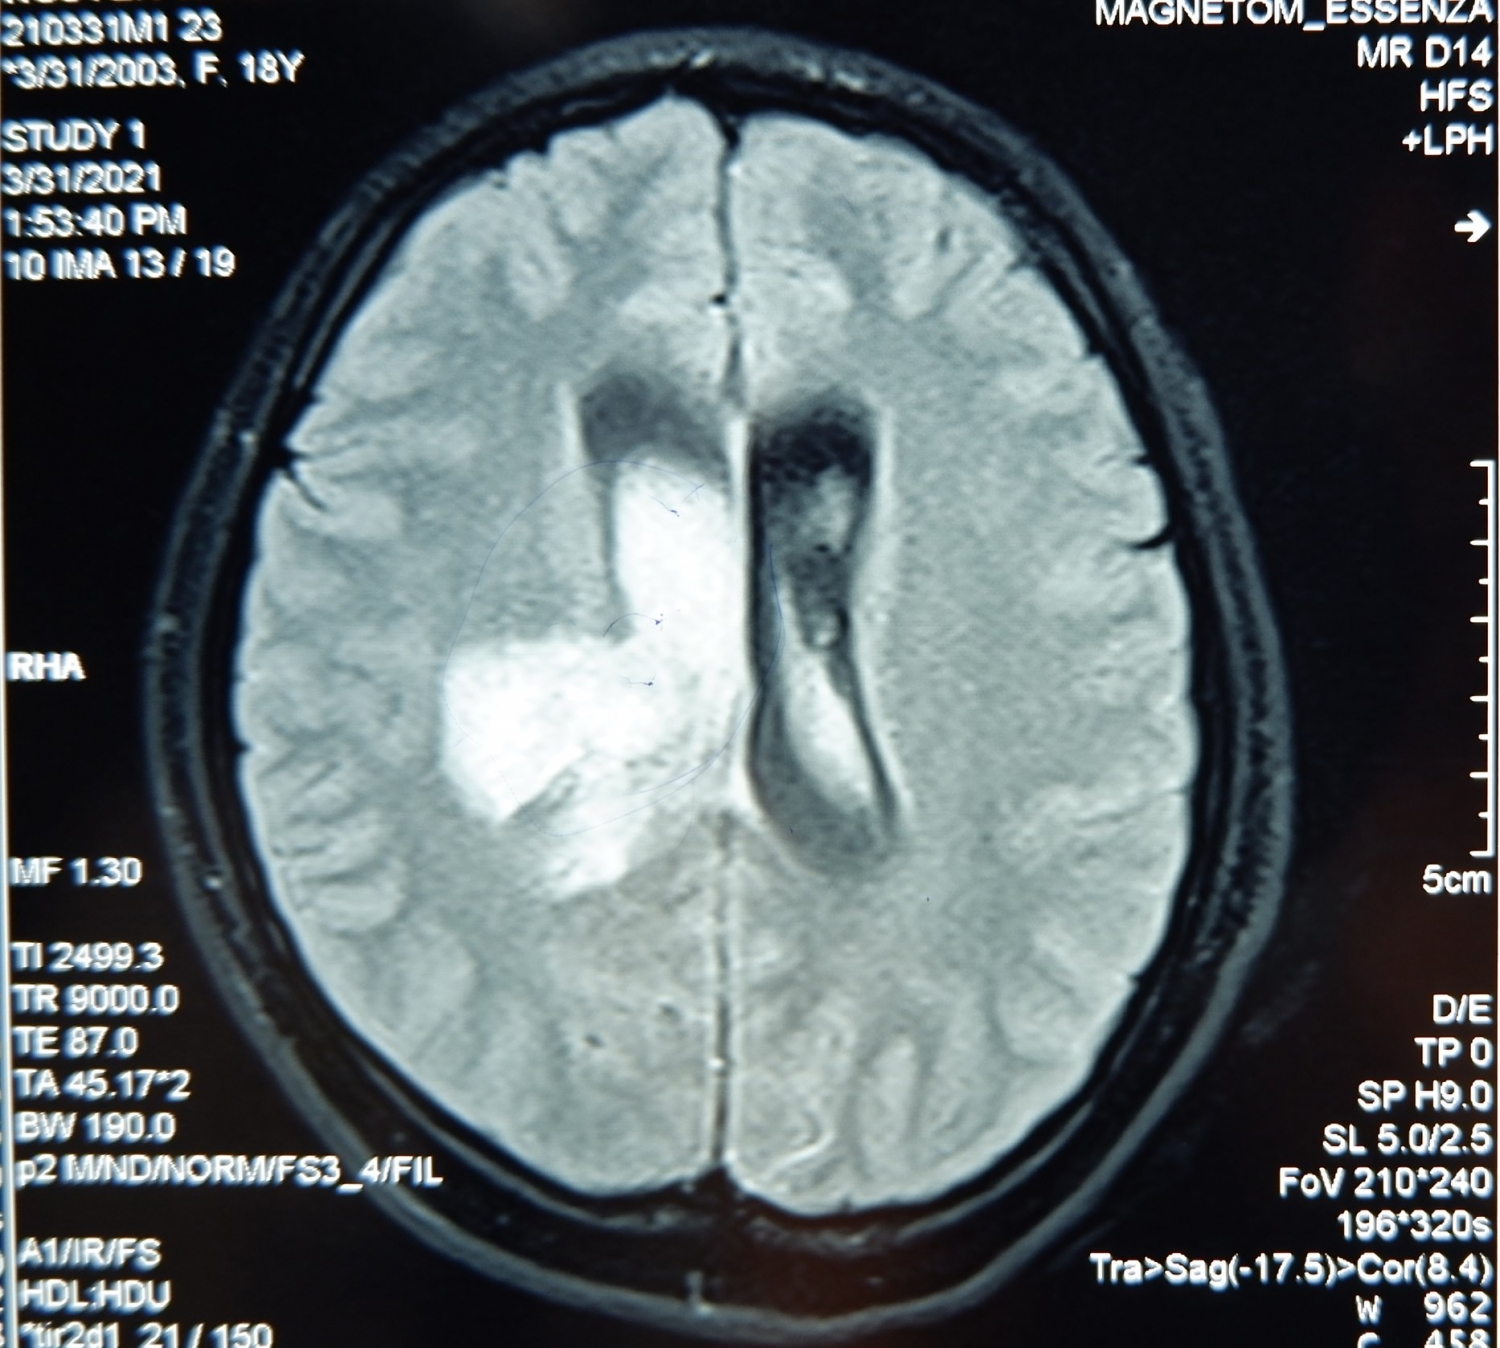

Gia đình đã lập tức đưa em K. tới BVXA cấp cứu, kết quả chụp CT não cho thấy tình trạng xuất huyết não đồi thị bên phải, xuất huyết não thất lượng nhiều kèm dãn não thất cấp. Các bác sĩ kết luận em K. bị đột quỵ do xuất huyết não đồi thị - xuất huyết não thất - dãn não thất cấp có chỉ định phẫu thuật cấp cứu khẩn cấp.

| Kết quả chụp cắt lớp vi tính (CT) não cho thấy tình trạng xuất huyết não đồi thị bên phải, xuất huyết não thất lượng nhiều kèm dãn não thất cấp |

Sau phẫu thuật bệnh nhân được theo dõi sát, kết quả chụp CT kiểm tra mỗi 24 giờ thấy khối máu trong não thất tan nhiều và lưu thông dịch não tuỷ trở lại ổn định.